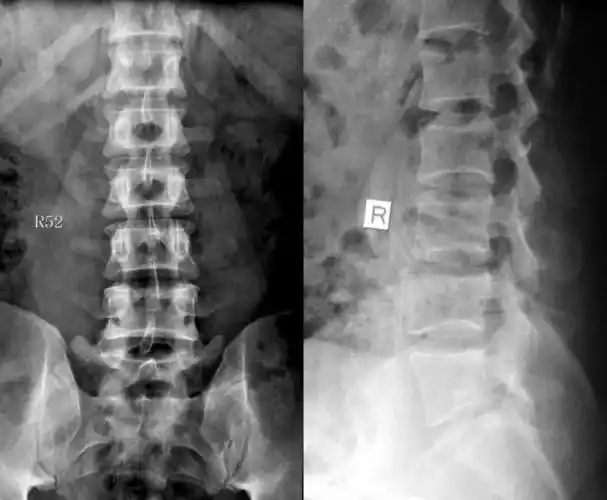

腰骶骨移行椎你是如何判断的